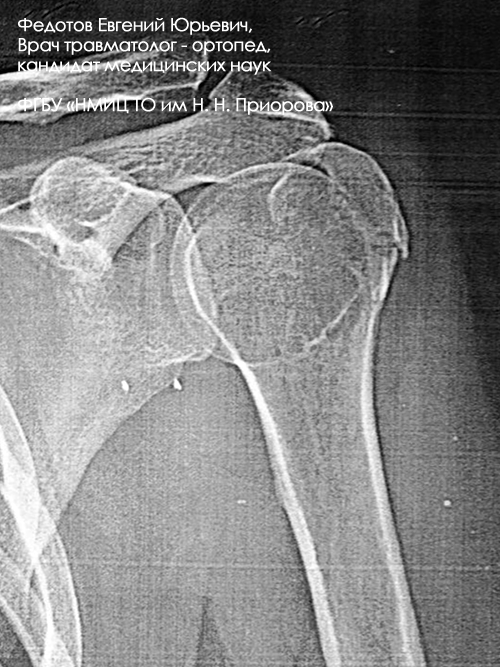

Перелом большого бугорка плечевой кости

Операция: Открытая репозиция, анкерная фиксация большого бугорка плечевой кости.

Неправильно срастающийся оскольчатый перелом большого бугорка плечевой кости.

Операция: Открытая репозиция большого бугорка плечевой кости с фиксацией анкерным швом